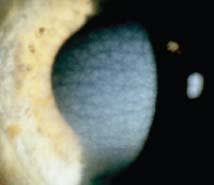

It is said that a picture is worth a thousand words; the best way to diagnose a corneal dystrophy is often to compare the eye that you see with images of diagnosed corneal dystrophies. This allows you to match the cornea that you are examining to a variety of images to ensure the proper diagnosis. Figures 1 through 24 can be considered good examples of many of the dystrophies listed in the tables and may be a useful reference in making a diagnosis. All of these figures except for Figure 12 originally appeared in the December 2008 supplement of the journal Cornea and are reprinted with permission of The Cornea Society, Copyright 2008, all rights reserved.

Figure 16. Congenital stromal dystrophy. |